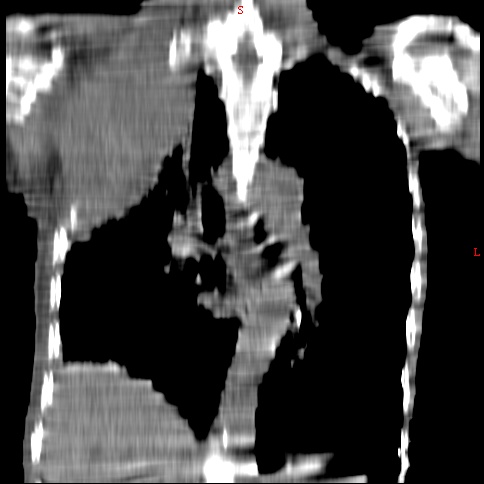

患者男,81岁,咳喘10余年,继往结核病史,发现胸部体表肿物(具体时间不详)就诊

右侧胸廓塌陷。右前上外侧胸壁软组织肿块,其内见有低密度影,肋骨呈溶骨性表现。右肺上叶见大量的间质纤维化表现。右侧膈肌上抬。

患者男,81岁,咳喘10余年,继往结核病史,发现胸部体表肿物

考虑:1、继发性结核,右结核性胸膜炎伴胸壁结核性感染

2、右侧胸壁恶性肿瘤。

肺尖巨大肿块影阴,胸壁受侵肋骨破坏,肿块密度不均且穿破胸壁入皮下,应该是:肺上沟癌;由于肺内有斑片状播散病灶,因此不排除胸壁结核。

患者男,81岁,咳喘10余年,继往结核病史,发现胸部体表肿物。

考虑:1 右侧胸壁恶性肿瘤(多考虑:胸膜间皮瘤)。

2 继发性结核,右结核性胸膜炎伴胸壁结核性感染。